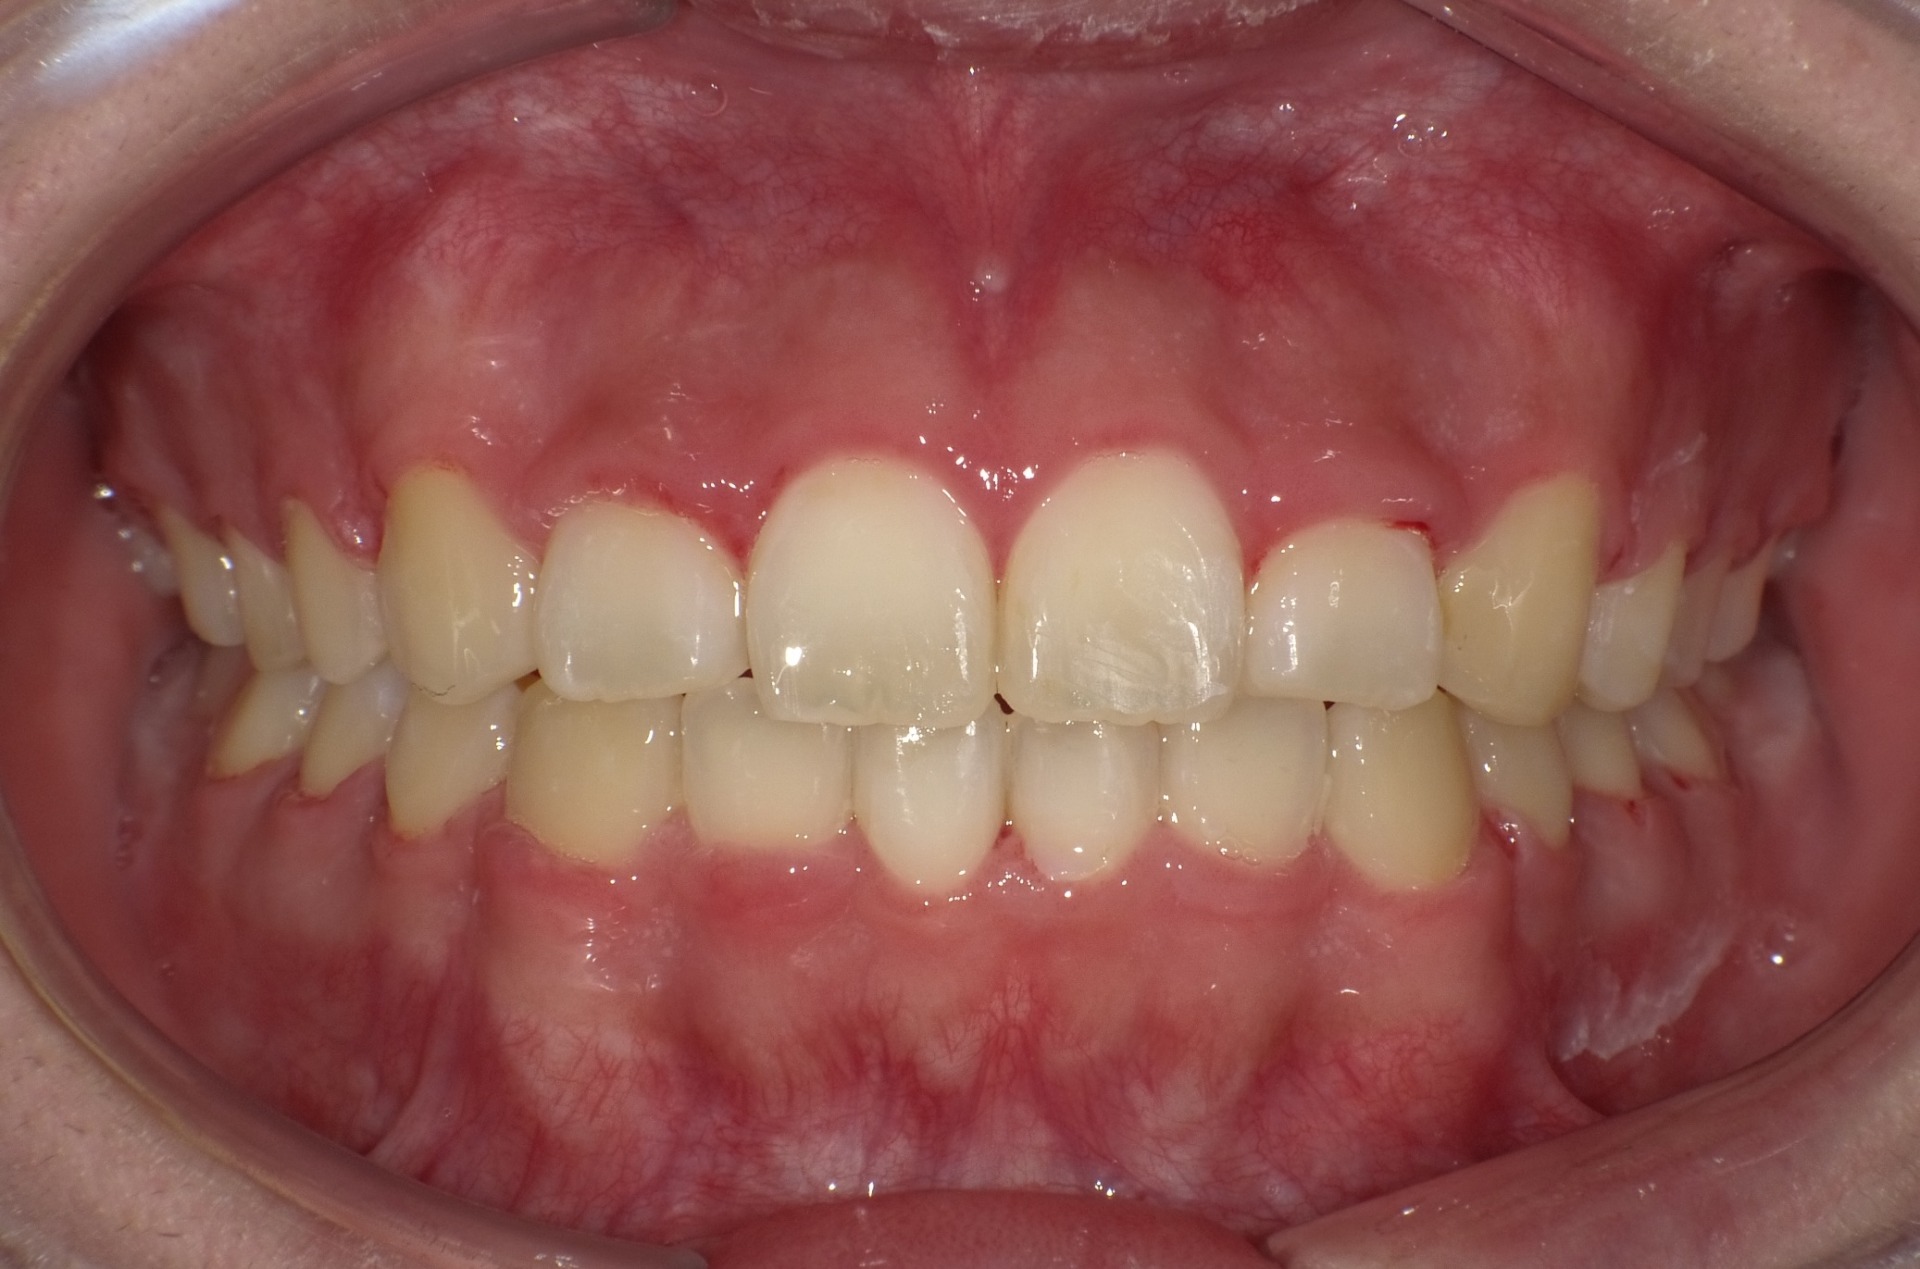

矯正前